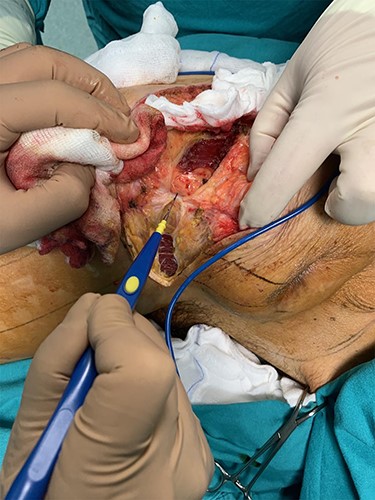

During the operation, surgeons exposed meticulously the liposarcoma that was utterly removed, and performed elective resection of the right iliac crest, the upper part of the sartorius muscle, part of the gluteus maximus muscle, and part of the muscles of the anterior abdominal wall in order to eliminate the potentiality of local recurrence of the liposarcoma (Figs. 5–7). The operation was uneventful, and two drainages were placed into the pelvic fossa. The drainages were removed the sixth postoperative day when the patient was finally discharged with instructions. The pathology report documented a well-differentiated liposarcoma of the right pelvic fossa. Finally, at the 6-month follow-up, the patient had no complication or recurrent lesions and oncologists declared that adjuvant therapy was not essential.

Elective resection of the right iliac crest and part of the right gluteus maximus muscle.

The resected liposarcoma with the adjacent tissues, for the elimination of the potentiality of local recurrence.